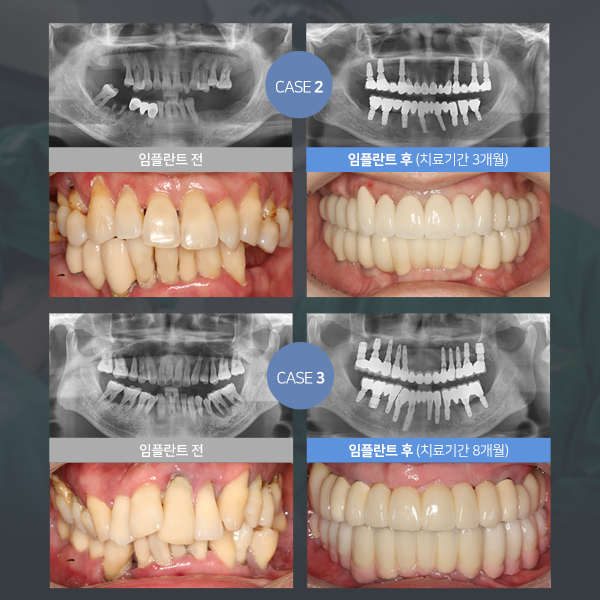

라임나무치과는

고난이도 및 다양한 케이스의 임플란트 시술이 가능합니다.

20년간의 풍부한 경험과 노하우를 갖춘

대표원장님께서 직접 시술을 진행해드립니다!